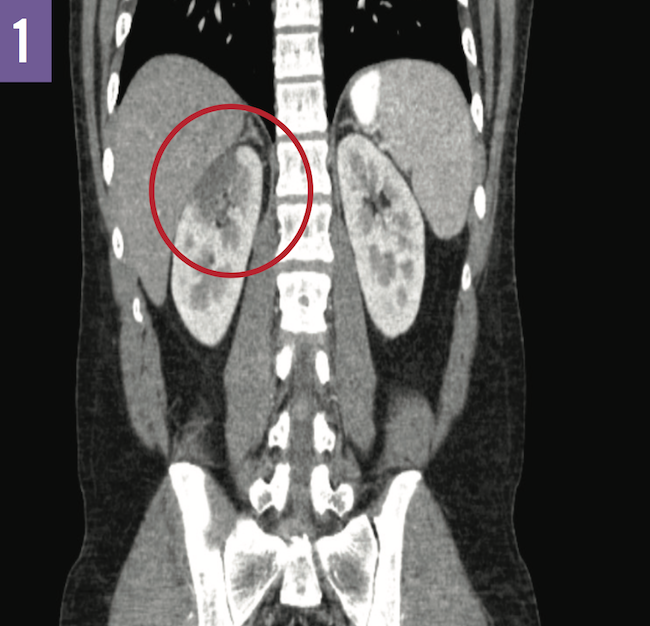

A number of imaging studies were done during his hospital stay. Computed tomography scans of the abdomen and pelvis were suggestive of a renal infarct as opposed to pyelonephritis (Figure 1). Transthoracic and transesophageal echocardiography revealed no apparent thrombi. Magnetic resonance angiography of the abdomen showed evidence of renal upper pole avascularization without abnormalities of the renal arteries (Figure 2).